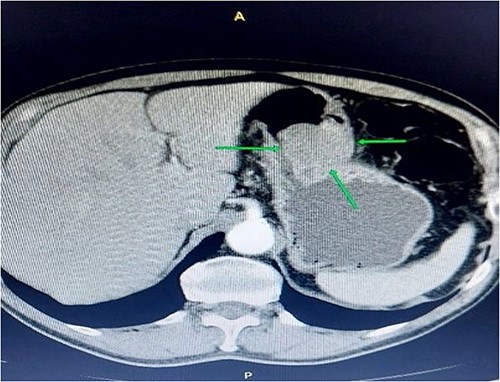

A 68-year-old man was referred to the gastroenterology department because of lower abdominal discomfort for the past 6 weeks. He was asymptomatic for gastric lesions, and a physical examination of the abdomen showed no evidence of tenderness or a palpable mass. The medical history was unremarkable. He had no previous surgical treatments or other illnesses. Routine blood tests were unremarkable. The patient underwent a contrast-enhanced computed tomography (CT) scan of the abdomen and was found to have a significant submucosal mass, ~5–7 cm, toward the antral region and along the greater curvature of the gastric body (Fig. 1).

Contrast-enhanced abdominal computerized tomography. The axial section presents a tumor mass measuring 55*85 mm in diameter.